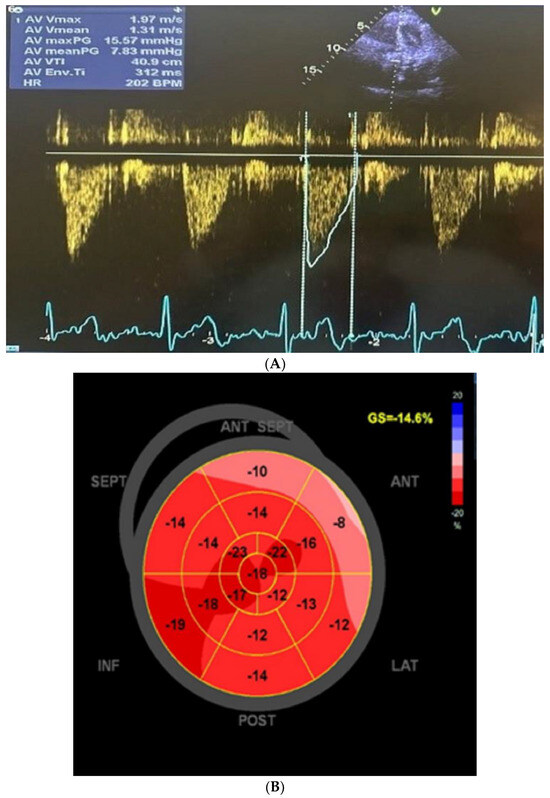

3. Cardiac Findings